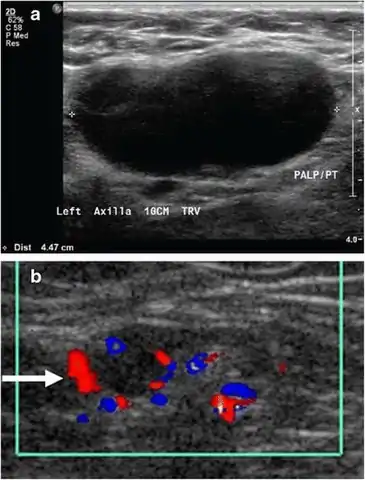

Superficial soft tissues

Doppler ultrasonography can help distinguishing benign from malignant soft tissue lumps.[15] Power Doppler is useful in assessing tendon and joints inflammation such as paratenonitis.[16]

15. Dialani V, James DF, Slanetz PJ (April 2015). "A practical approach to imaging the axilla". Insights into Imaging. 6 (2): 217–29. doi:10.1007/s13244-014-0367-8. PMC 4376818. PMID 25534139. Creative Commons attribution license